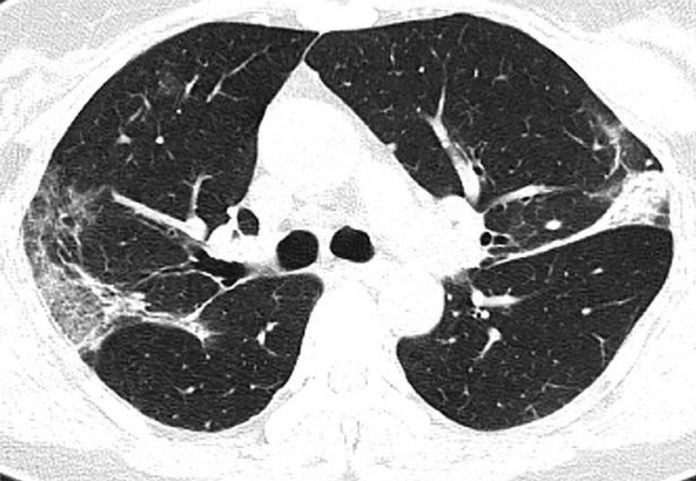

Στις ακτινογραφίες διακρίνονται κάποια άσπρα σημάδια, χαμηλά στους πνεύμονες. Περιγράφονται ως υγρό στις κυψέλες του πνεύμονα.

Αυτή είναι η ακτινογραφία μιας 45χρονης, με τα άσπρα σημάδια που διακρίνονται να είναι η ζημιά που έχει κάνει ο covid-19.